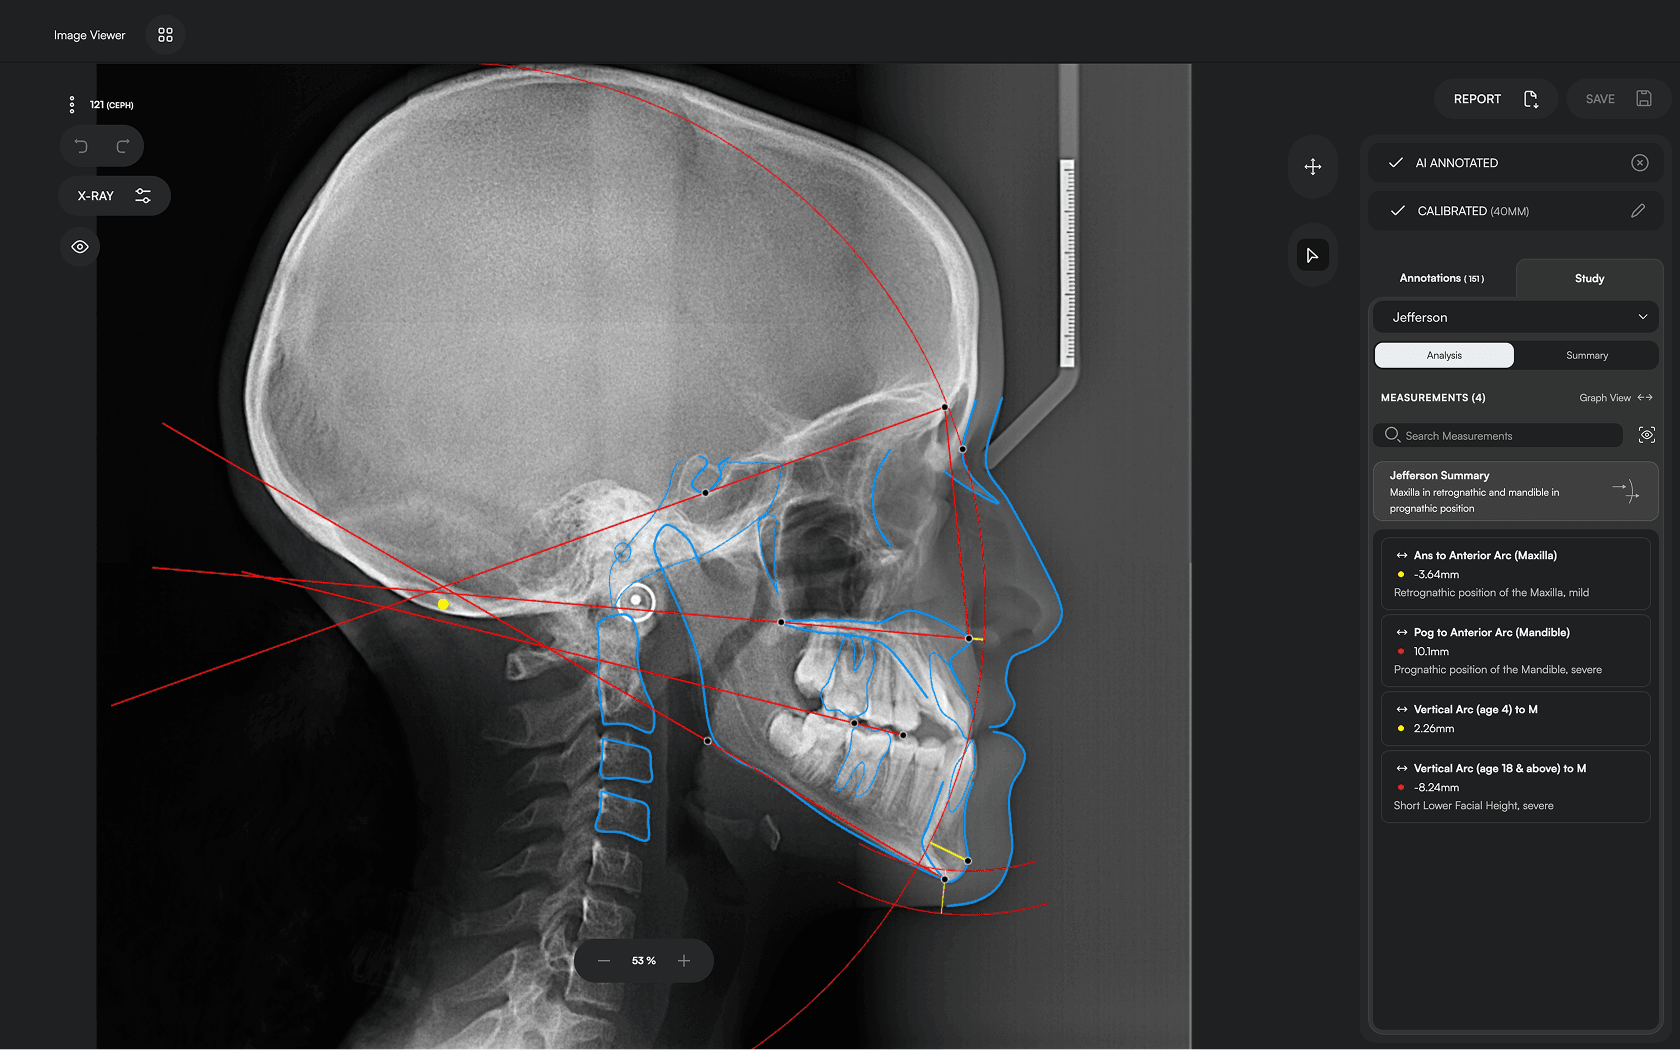

Access automated studies like Steiner and Jefferson to assist in clinical assessment and enhance case evaluations.

Experience a comprehensive assessment of skeletal, dental, and soft tissue discrepancies.

Clear Reporting

Create concise, clear reports to build confidence, enhance patient

communication and ensure transparency.